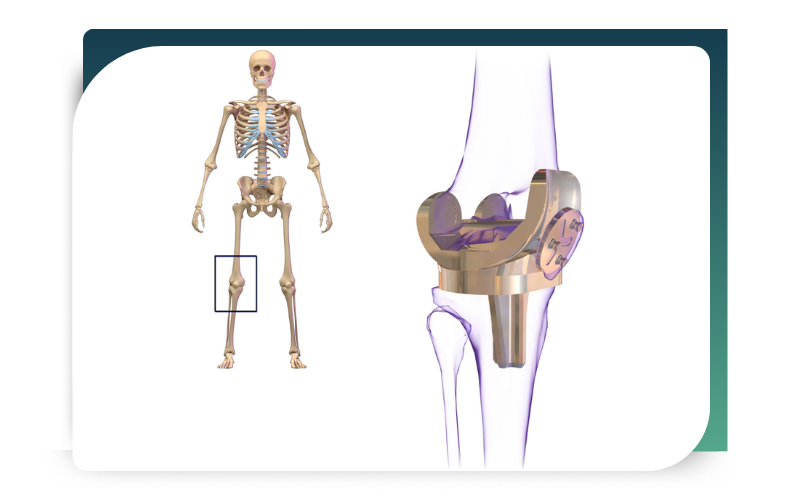

Knee replacement offers several life-changing benefits. Most importantly, it helps patients regain comfort and confidence in their daily lives. Some of the key advantages include:

In addition, most patients report dramatic improvement within just a few weeks after surgery. Over time, strength and flexibility continue to improve with proper rehabilitation. Furthermore, modern implants are highly durable and, with proper care and regular follow-ups, they can last 15–20 years or even longer. Therefore, knee replacement not only relieves pain but also provides long-term functional benefits.